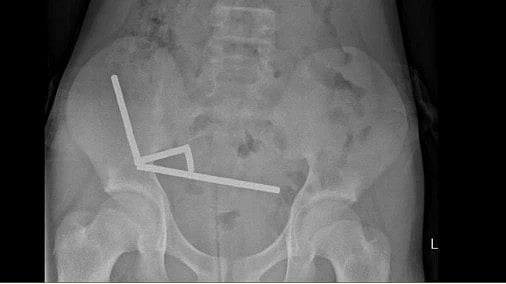

The boy was admitted to the hospital for four days after admitting to swallowing 80–100 magnets reportedly purchased from Temu. Abdominal X-rays revealed four linear chains of magnets in the right lower quadrant of the abdomen. The magnets were located in separate parts of the bowel but adhered together due to their magnetic forces.

The patient underwent a laparotomy, which revealed multiple chains of magnets in different segments of the small bowel and caecum, causing pressure necrosis at multiple points in the right lower quadrant. Surgeons performed an ileocolic resection and two small bowel wedge resections to remove the magnets. Intraoperative imaging confirmed that no further magnets remained. The boy was discharged on post-operative day eight after successfully resuming his diet.